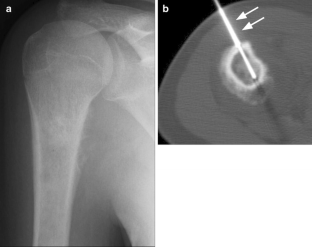

Fig. 1

Fig. 2

Fig. 3

Fig. 4

Fig. 5

Fig. 6

Fig. 7

Fig. 8